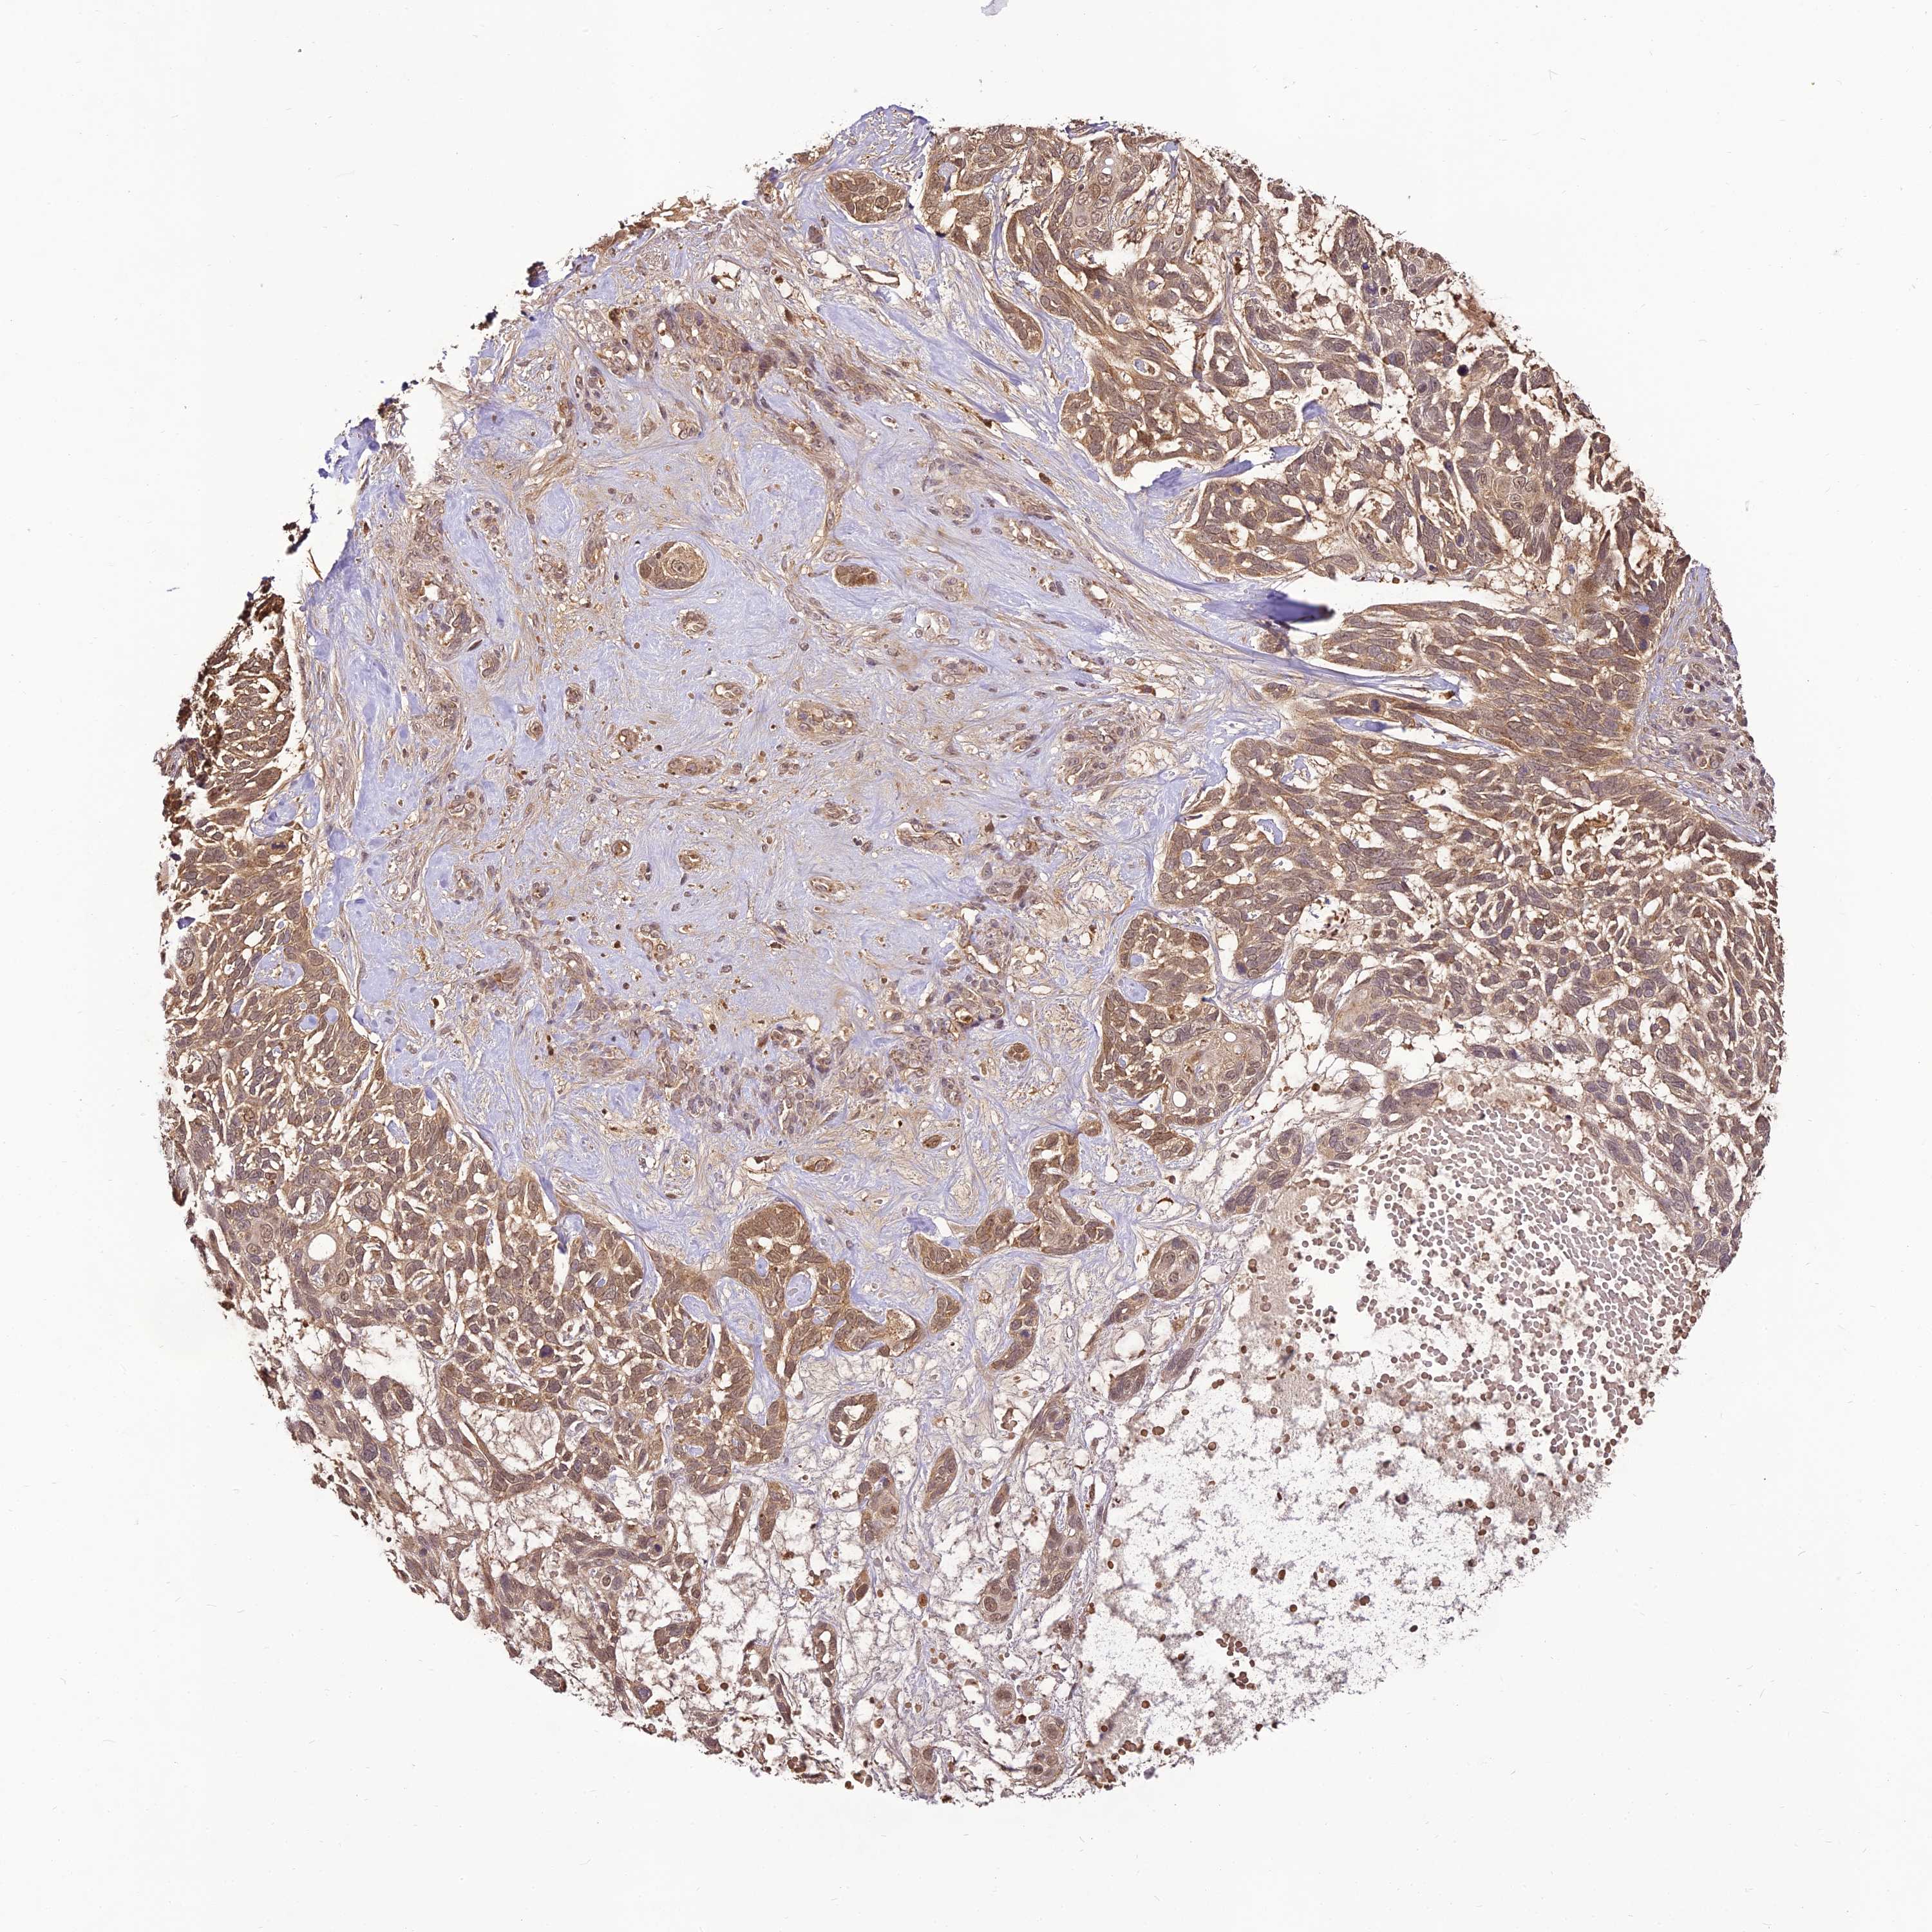

SKIN CANCER - Protein expressioni

A mouse-over function shows sample information and annotation data. Click on an image to view it in a full screen mode. Samples can be filtered based on level of antibody staining by selecting one or several of the following categories: high, medium, low and not detected. The assay and annotation is described here.

Antibody staining in the annotated cell types in the current human tissue is reported as not detected, low, medium, or high, based on conventional immunohistochemistry profiling in selected tissues. This score is based on the combination of the staining intensity and fraction of stained cells.

Each image is clickable and will lead to virtual microscopy that enables deeper exploration of all samples and also displays staining intensity scores, fraction scores and subcellular localization as well as patient and tissue information for each sample.

Antibody HPA039911

Staining

High

Medium

Low

Not detected

Intensity

Strong

Moderate

Weak

Negative

Quantity

>75%

75%-25%

<25%

None

Location

Nuclear

Cytoplasmic/membranous

Cytoplasmic/membranous,nuclear

Basal cell carcinoma

Squamous cell carcinoma, NOS

Squamous cell carcinoma, metastatic, NOS